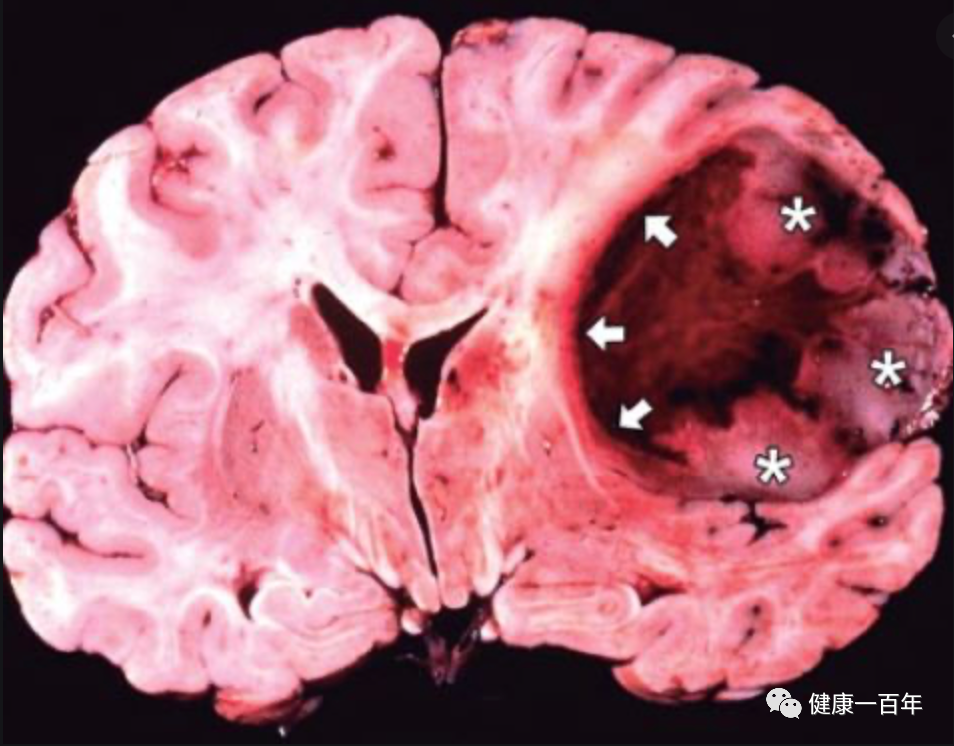

脑肿瘤,尤其是胶质瘤,则一直都是最致命的癌症类型。